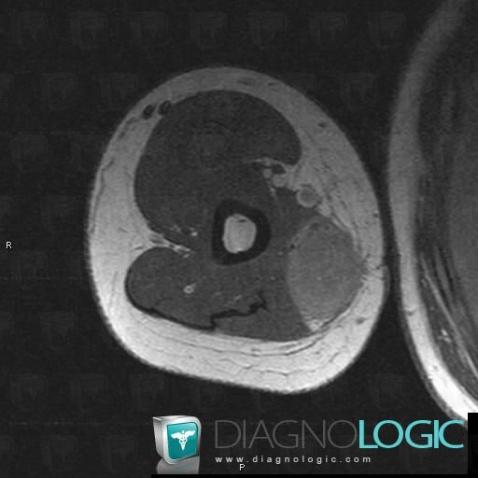

Synovial sarcoma, Other soft tissues/nerves - Arm, MRI

Here is the specific information in the key image above:

- Diagnosis Synovial sarcoma, Location(s) Other soft tissues/nerves - Arm, with gamuts Cystic and cystic-like soft tissue mass